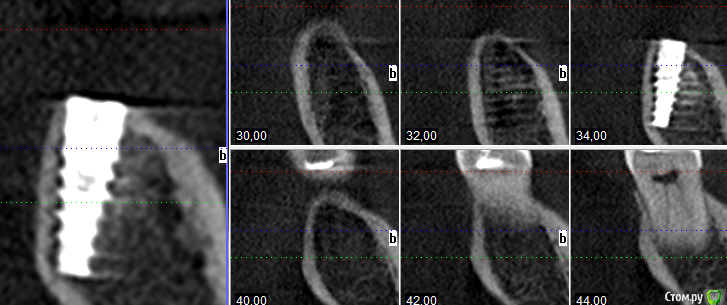

Елена83 Опубликовано 5 февраля, 2016 Поделиться Опубликовано 5 февраля, 2016 Нижний 6 зуб. Правильно ли установлен имплант?прошло 2мес Ссылка на комментарий

Елена83 Опубликовано 5 февраля, 2016 Автор Поделиться Опубликовано 5 февраля, 2016 Здравствуйте чтобы оценить нужно смотреть по отношению к другим зубаместь другие нарезки?Есть в таком виде Дело в том что у меня бывает бруксизм при нервном перенапряжении. Редко, но случаи были. Поэтому страшновато Ссылка на комментарий